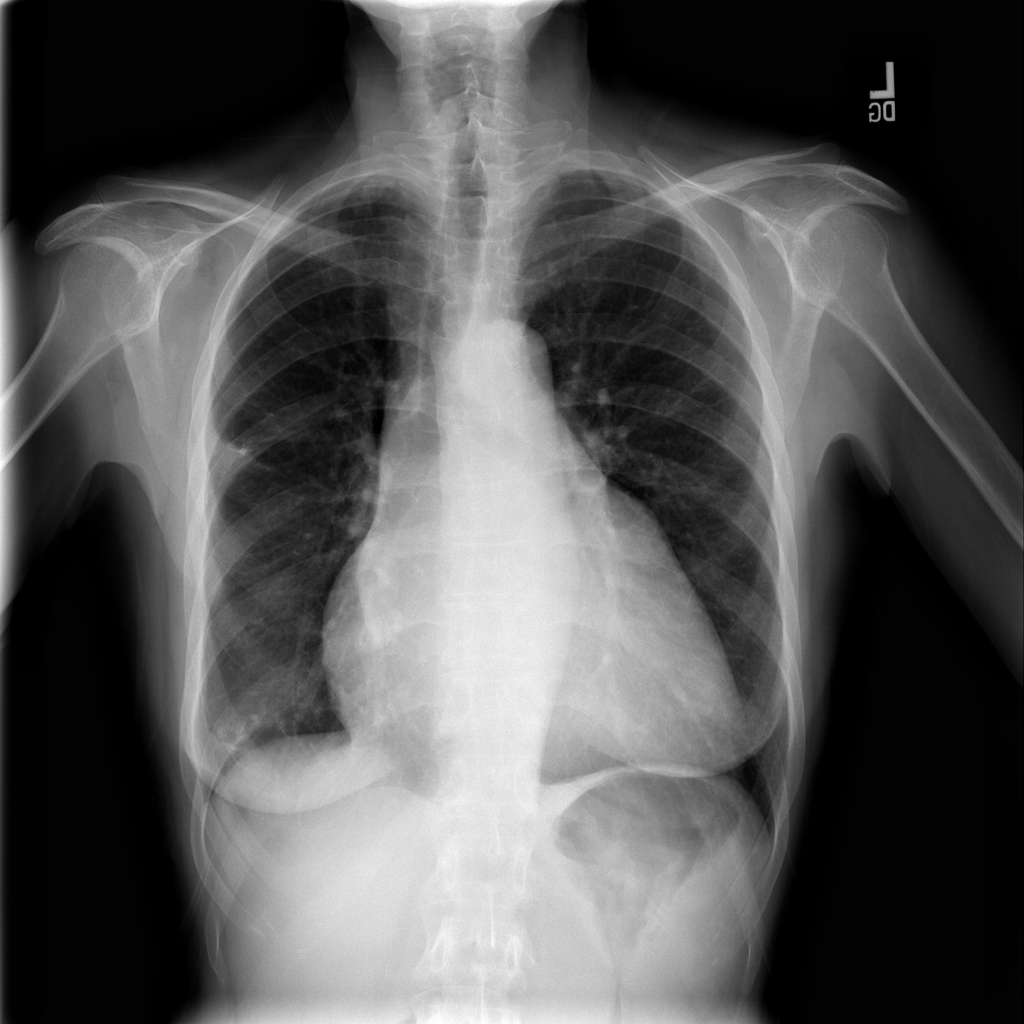

PAT-4639 · IMG-020Pneumothorax

PAT-4639 · IMG-020

PA